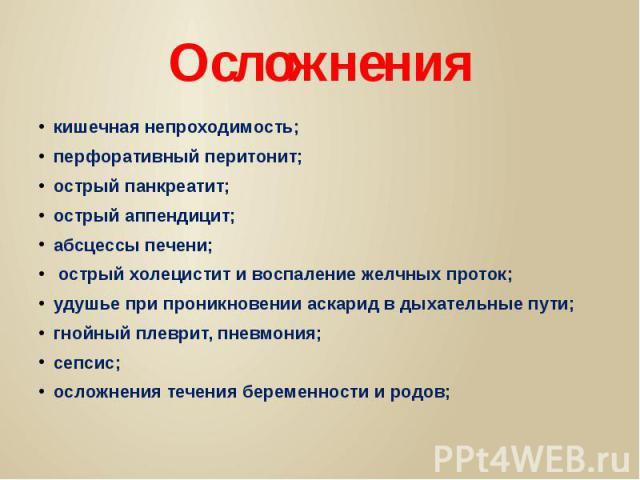

Иллюстрации и информация о симптомах острого кишечного непроходимости